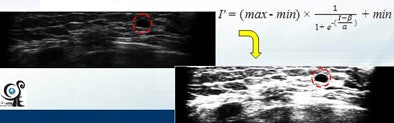

"Images are preprocessed by removing black regions, subsampling to reduce the detection time, and sigmoid filtering to enhance the boundary between tumor and normal tissue," Chang said. "A 3D fuzzy technique is adopted to detect tumor regions in the breast."

| Images are preprocessed by removing black regions, subsampling to reduce detection time, and sigmoid filtering to enhance the boundary between tumor and normal tissue. |